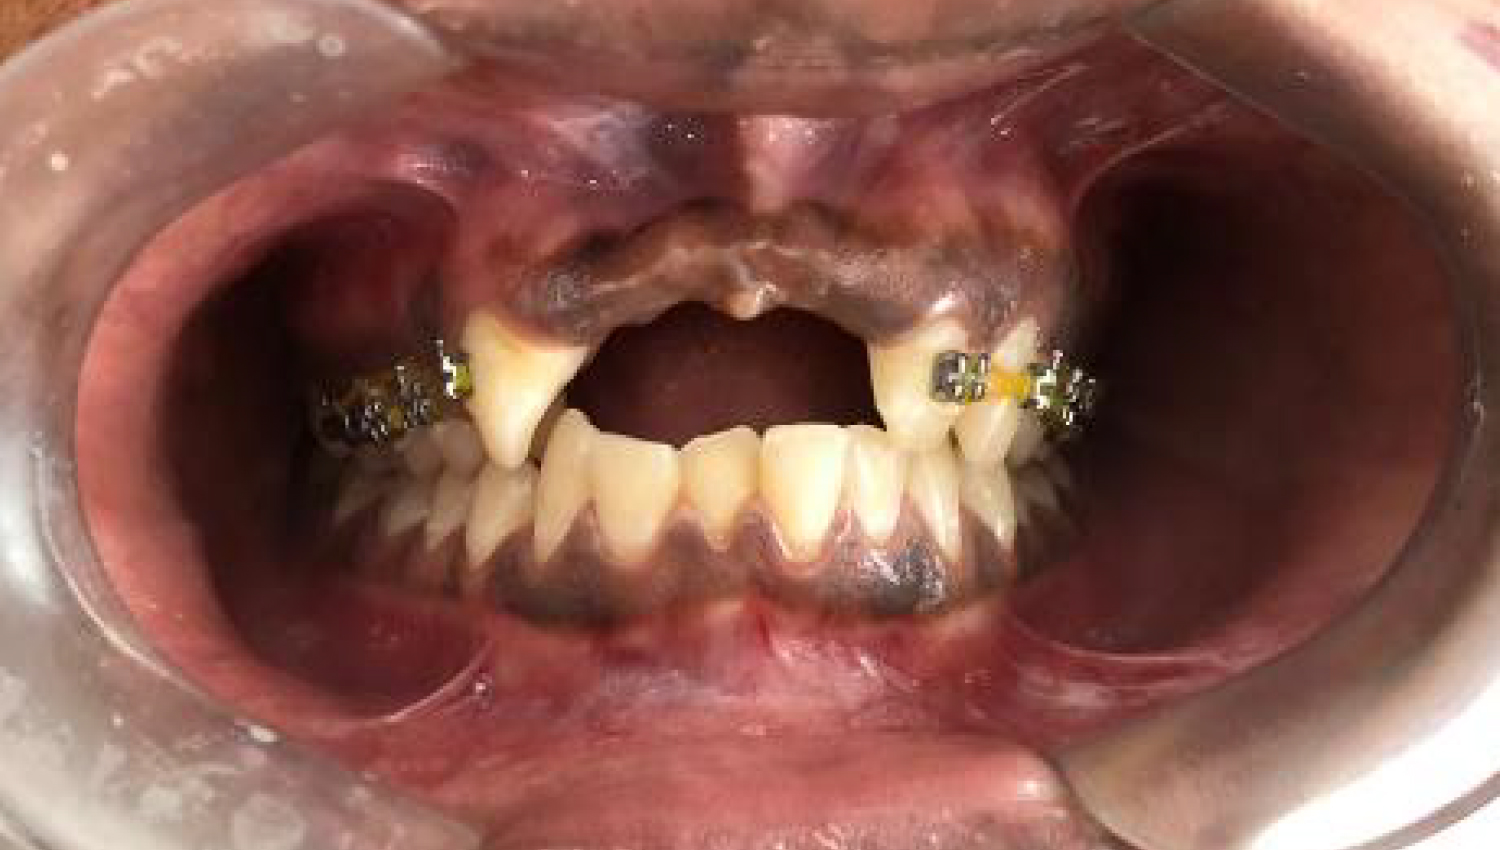

2.Complex Three Dimensional Augmentation procedure was applied to the patient with Khoury's Technique. Powerbone Gel and Cortical plate products were used during the process.

3.Final clinical view.